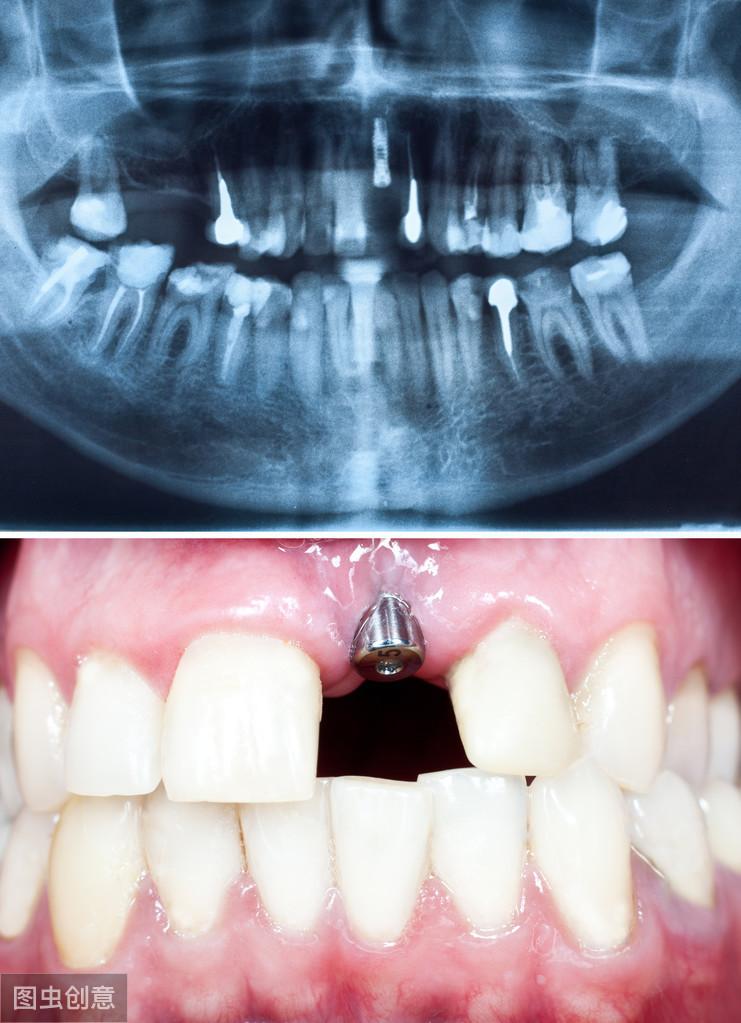

如果沒有需要調(diào)節(jié)的口腔問題,就可以進(jìn)行牙槽骨估值檢測(cè),因?yàn)榉N植體是直接植入牙槽骨的,所以骨質(zhì)的好壞也是決定能否接受牙齒種植的關(guān)鍵性因素。

3. 植入種植體:這個(gè)時(shí)候開始進(jìn)行第一期手術(shù),手術(shù)將在牙槽骨上選擇合適的位置打洞,植入種植體后縫合創(chuàng)口,正常情況下整場(chǎng)手術(shù)時(shí)長在半個(gè)小時(shí)左右。

5. 等待骨愈合:種植體植入牙槽骨后需要一個(gè)相互適應(yīng)的過程,在這個(gè)過程里種植體會(huì)逐步的與骨組織結(jié)合,根據(jù)受力和其他影響因素,骨結(jié)合所需的時(shí)間也是因人而異,大概在3-6個(gè)月左右。